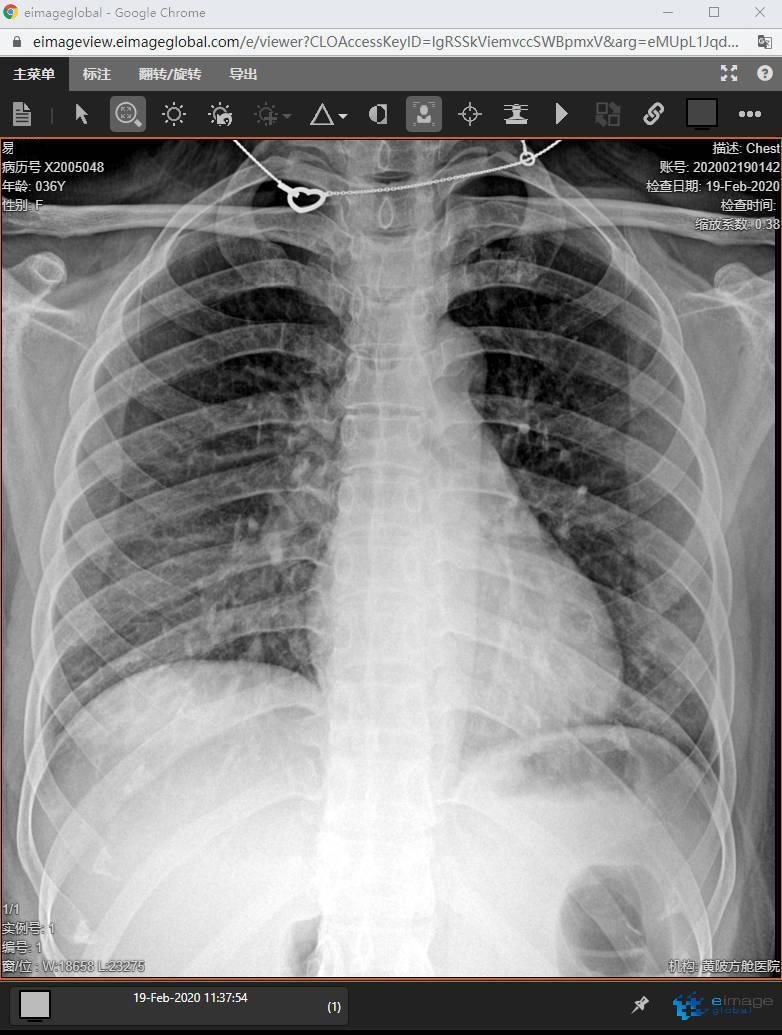

2月19日,在武(wu)漢黃(huang)陂(po)區的(de)(de)“黃(huang)陂(po)方(fang)艙醫院(yuan)”簡(jian)陋(lou)的(de)(de)DR工作室里,浙(zhe)江(jiang)省人民醫院(yuan)醫療隊(dui)俞(yu)亮技師剛剛給(gei)36歲的(de)(de)“新冠肺(fei)炎”患者易女士拍完胸片(pian),她的(de)(de)影像被迅速地通過網絡傳輸(shu)到云端服務(wu)器(qi)。千里之(zhi)外(wai)的(de)(de)“黃(huang)陂(po)方(fang)艙醫院(yuan)”后方(fang)大本營、浙(zhe)江(jiang)省人民醫院(yuan)放(fang)(fang)射科(ke)龔(gong)向(xiang)陽主任等專家組立刻借助遠程影像系統,對易女士的(de)(de)胸片(pian)進(jin)行認(ren)真解讀,并將診斷意見發送給(gei)身在武(wu)漢的(de)(de)緊急醫學(xue)救援隊(dui)員(yuan)隊(dui)員(yuan)、放(fang)(fang)射科(ke)管政醫生(sheng)。

位于武漢市(shi)黃(huang)陂區的(de)(de)(de)“黃(huang)陂方(fang)艙醫(yi)(yi)院(yuan)(yuan)”,是由浙江省人民醫(yi)(yi)院(yuan)(yuan)國家緊(jin)急醫(yi)(yi)學救援隊全面接(jie)管(guan)的(de)(de)(de)一家“方(fang)艙醫(yi)(yi)院(yuan)(yuan)”。雖然以(yi)接(jie)收輕(qing)癥患者為主,但是需要及時(shi)發現病情變化,及時(shi)將重癥患者轉往有(you)救治能(neng)力的(de)(de)(de)醫(yi)(yi)院(yuan)(yuan)。胸(xiong)部(bu)影像檢(jian)查是評估(gu)病情變化的(de)(de)(de)有(you)效(xiao)手段,在臨(lin)時(shi)改建(jian)的(de)(de)(de)方(fang)艙醫(yi)(yi)院(yuan)(yuan)里,胸(xiong)部(bu)影像學檢(jian)查意義重大,它能(neng)為臨(lin)床醫(yi)(yi)生提供更(geng)清晰的(de)(de)(de)診療依據。

然而,在黃(huang)陂區體(ti)育(yu)館改建的(de)方(fang)艙(cang)醫院(yuan),實現(xian)這一切并不容易,一切似乎回(hui)到了30年(nian)前,簡易分隔的(de)機房、筆記本(ben)連接的(de)顯示器(qi)、缺乏嚴(yan)密(mi)防護的(de)工作人員,放射科管政、俞亮克(ke)服(fu)艱難困苦,創(chuang)造(zao)條件(jian),成功為患者完成了一次次X線檢查。